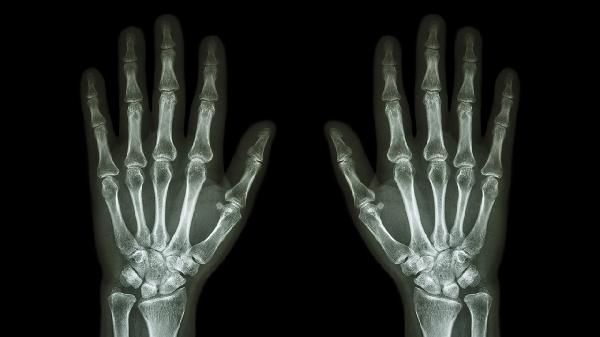

小拇指关节疼痛肿胀是怎么回事

小拇指关节疼痛肿胀可能与外伤、骨关节炎、类风湿关节炎、痛风性关节炎、腱鞘炎等因素有关,可通过休息制动、药物治疗、物理治疗等方式缓解。建议及时就医明确病因,遵医嘱干预。